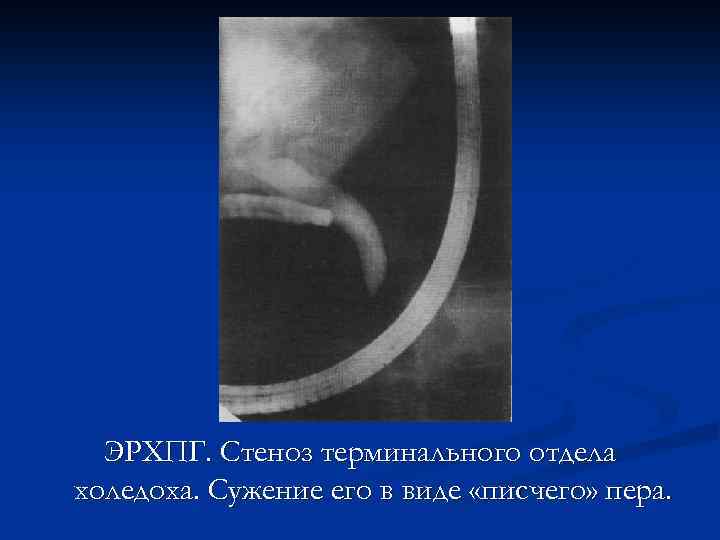

ЭРХПГ. Стеноз терминального отдела холедоха. Сужение его в виде «писчего» пера.

ЭРХПГ. Стеноз терминального отдела холедоха. Сужение его в виде «писчего» пера.

ЭРХПГ. Стеноз терминального отдела холедоха. Сужение его в виде «писчего» пера.

ЭРХПГ. Стеноз терминального отдела холедоха. Сужение его в виде «писчего» пера.